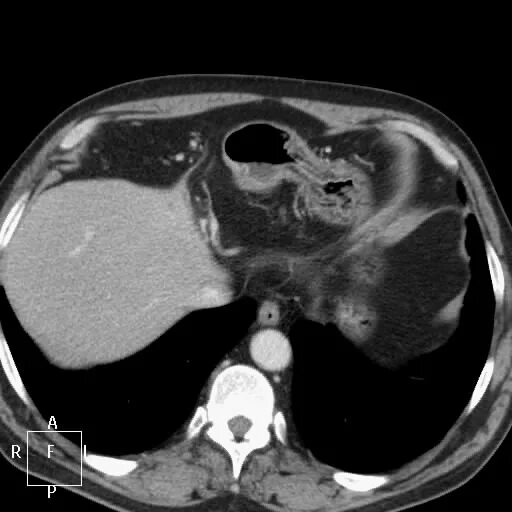

Болит кт